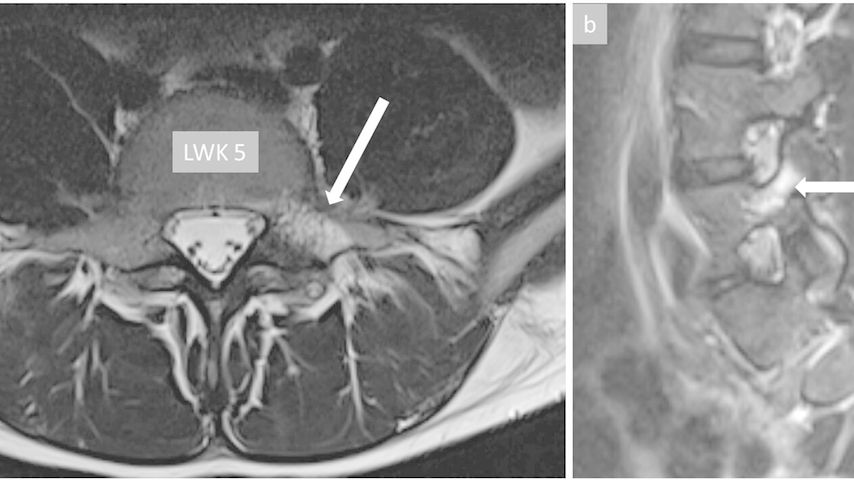

Bei klinischem Verdacht auf eine Spondylolyse ist zur weiteren Abklärung ein konventionelles Röntgenbild der LWS anteroposterior (ap) und lateral stehend weiterhin die initiale Modalität der Wahl.9,10 Nebst der gesuchten Spondyloyse lassen sich allfällig vorhandene knöchern-dysplastische Veränderungen nachweisen. Ausserdem lässt sich das tatsächliche Ausmass einer möglichen Spondylolisthese gegenüber im Liegen durchgeführten Schichtbildverfahren mit teilweise reponiertem Wirbelgleiten adäquat beurteilen. Eine ergänzende Magnetresonanztomografie (MRT) der LWS ist insbesondere bei einer akuten Schmerzanamnese oder nicht konklusivem konventionellem Röntgen sinnvoll, da mit dieser Modalität ein Ödem der betroffenen Pars interarticularis oder des/der angrenzenden Pedikel/-s nachgewiesen und gleichzeitig andere Pathologien, wie beispielweise Diskopathien, ausgeschlossen werden können. Ausserdem erlaubt die MRT-Untersuchung die Objektivierung einer sogenannten Prälyse, welche als Vorstufe einer etablierten Spondylolyse verstanden wird und sich durch ein isoliertes Pars-/Pedikelödem ohne knöcherne Unterbrechung darstellt (Abb. 3). Mit der zunehmenden Verfügbarkeit von speziellen MRT-Sequenzen, sogenannten «Black bone»-Sequenzen, welche eine sehr gute Darstellung der knöchernen Strukturen ermöglichen, sinkt die Indikation für eine zusätzliche strahlenintensive Computertomografie stetig.11 Die früher regelmässig durchgeführten und auch in der aktuellen Literatur weiterhin oft zitierten konventionellen Schrägaufnahmen bringen keinen relevanten zusätzlichen Nutzen und sollten aufgrund der hohen Strahlenbelastung nicht mehr gemacht werden.12

Abb. 3: Bild (a) zeigt einen axialen und Bild (b) einen sagittalen Schnitt einer MRT-Untersuchung mit Darstellung eines Ödems im Bereich des linken Pedikels von LWK5. Dieser Befund ist vereinbar mit einer Prälyse (Vorstufe einer Spondylolyse ohne nachweisbare knöcherne Unterbrechung der Pars interarticularis)